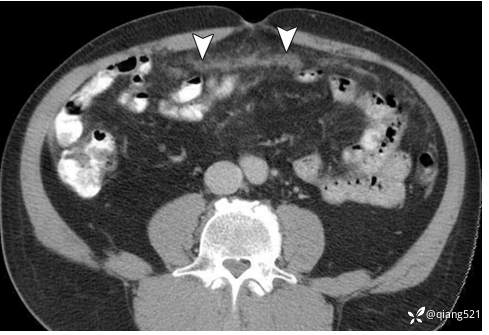

49 岁女性,患有原发性腹膜浆液性癌。 A-C 轴向 CECT 图像显示由于大量腹水导致腹胀,伴有腹膜软组织结节(A 中的箭头)和大网膜增厚(B 中的箭头)。卵巢未见异常(C)。 UT,子宫; LO,左卵巢。大网膜活检证实原发性腹膜浆液性癌